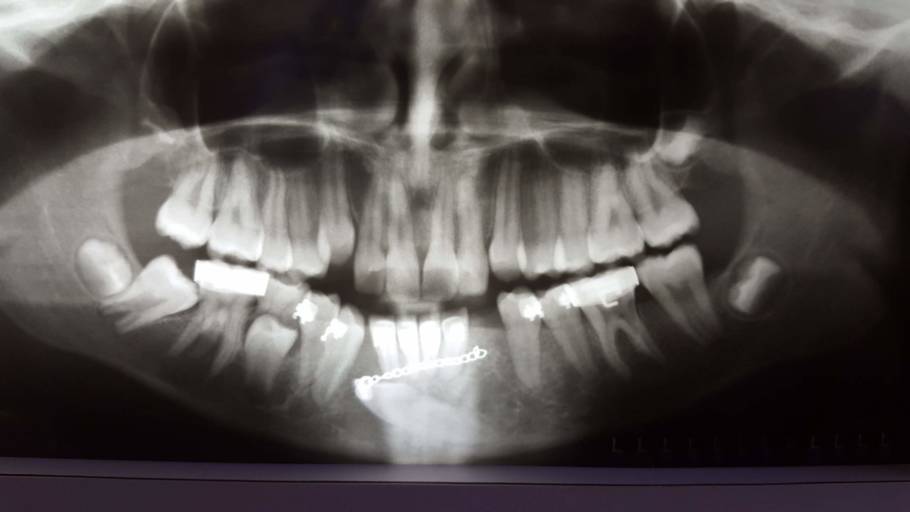

My teeth seem to be missaligned after an injury.

Hello, recently I suffered trauma to my jaw. I can close my jaw normally and my bite isn’t any different to me than before. But for the last 10 days( since the accident) I suffer from headaches every day, combined with jaw pain. Also, when I look at my teeth in the mirror they don’t look like before, they look missaligned (upper and lower jaw teeth as in the picture, they are not the same on the both sides). If the jaw is ‘moved’ a bit, can this be seen by an x-ray? How is it treated, can the jaw be put back into place ? Regards